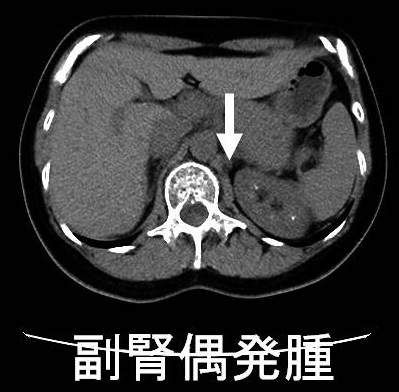

副腎は左右腎臓の上にあるのホルモン分泌臓器。副腎腫瘍はホルモンを作る機能性副腎腫瘍と作らない非ホルモン産生性腫瘍がある。腹部超音波検査やCTで偶然(1-5%、高齢者は10%)副腎腫瘍が発見される(副腎偶発腫瘍:インシデンタローマ)。約75%は副腎腺腫、約50%は非機能性副腎腺腫だが3cm以上なら副腎癌(副腎原発1%/転移性5%)の事がある。骨髄脂肪腫3%。機能性副腎腫瘍はクッシング症候群10%・褐色細胞腫10%・原発性アルドステロン症5%。単純CTでCT値が10HU未満の低吸収値になる副腎腫瘍は脂質を多く含む副腎腺腫。

腹部超音波検査やCTで偶然(1-5%、高齢者では10%)副腎腫瘍を発見される事があり、副腎偶発腫瘍(インシデンタローマ)と呼ばれます。